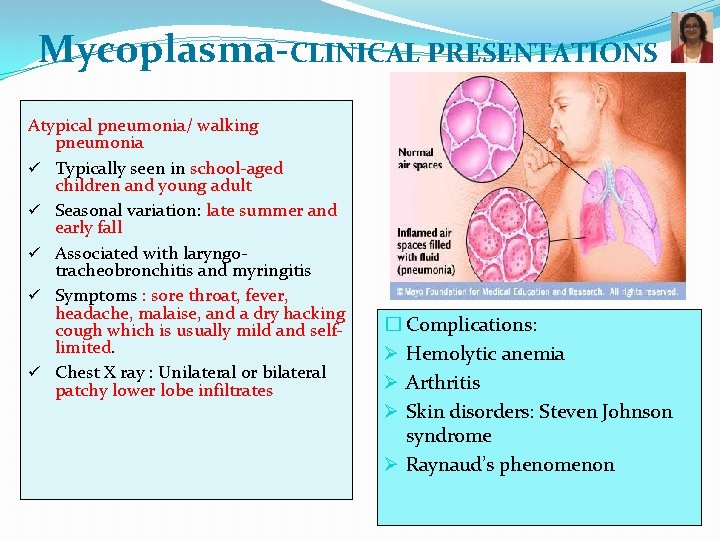

Mycoplasma-CLINICAL PRESENTATIONS Atypical pneumonia/ walking pneumonia ü Typically seen in school-aged children and young adult ü Seasonal variation: late summer and early fall ü Associated with laryngotracheobronchitis and myringitis ü Symptoms : sore throat, fever, headache, malaise, and a dry hacking cough which is usually mild and selflimited. ü Chest X ray : Unilateral or bilateral patchy lower lobe infiltrates � Complications: Ø Hemolytic anemia Ø Arthritis Ø Skin disorders: Steven Johnson syndrome Ø Raynaud’s phenomenon